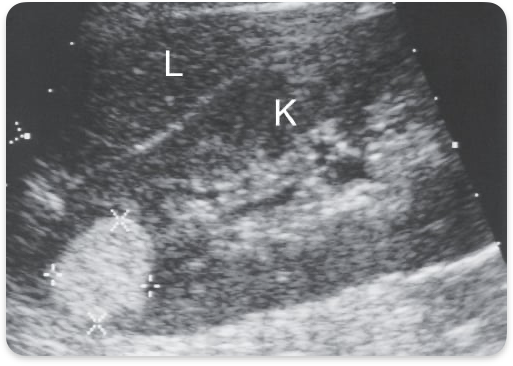

Chronic kidney failure. Small, echogenic. Cortical thinning. Loss of Cortico- medullary differentiation. Renal cysts